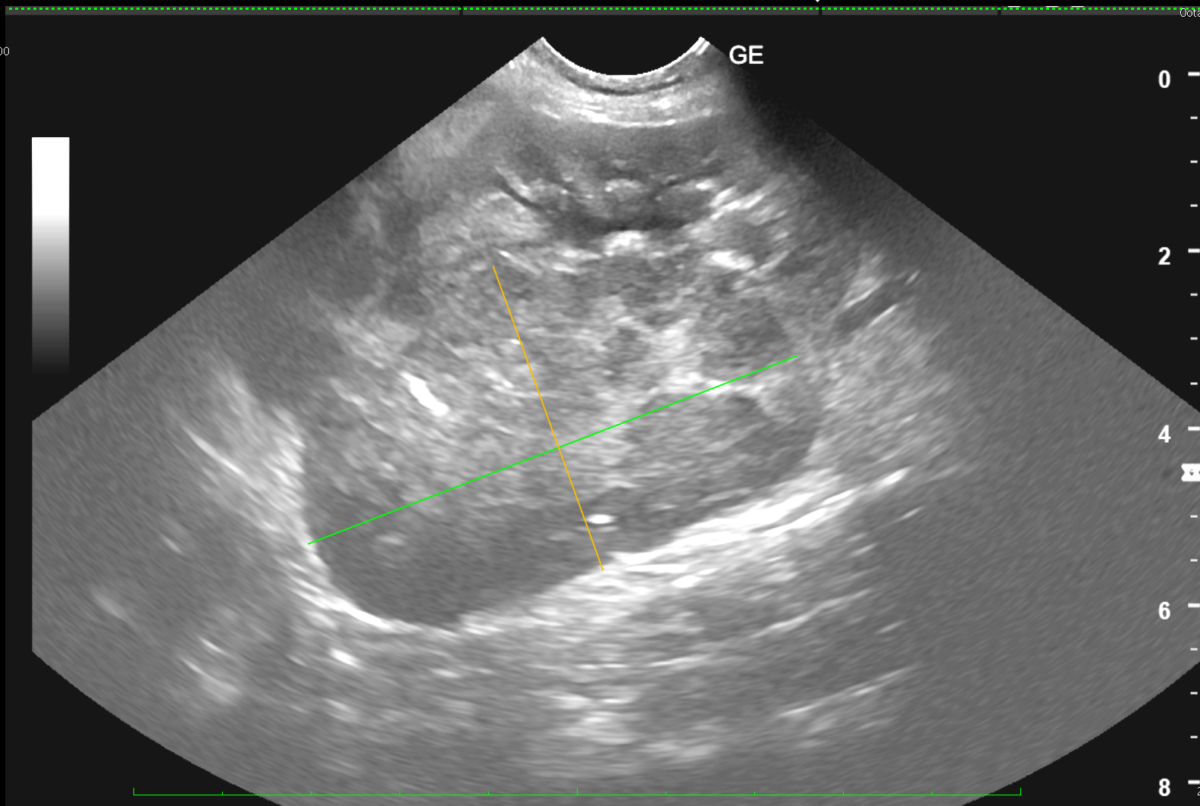

レントゲン検査、超音波検査を実施し、治療対象となる腫瘍のサイズを測定します。

また、化学療法実施後の効果測定(腫瘍の退縮は認められたか?)を実施します。

実際に、化学療法を実施した猫の超音波検査画像を記載しました。

化学療法実施前は、腎臓に明らかな腫瘤病変が認められましたが

化学療法実施1週間後には、腫瘤病変はほぼ確認できない程に退縮しています。

超音波検査画像 同症例 化学療法実施 1週間後